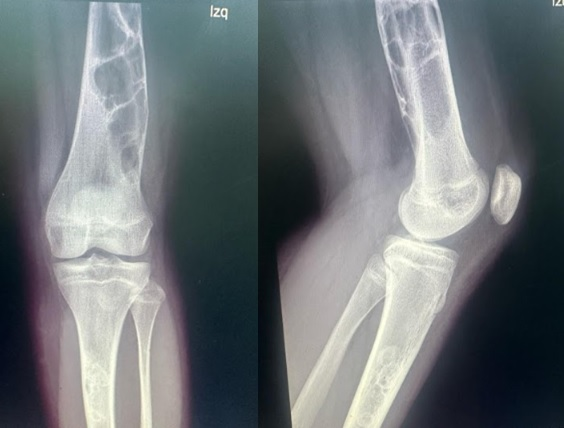

12 year-old female adolescent patient who is evaluated in the company of her mother referred for left knee pain in a study of 1 year of evolution and tumor of the distal femur and left proximal tibia, which is evident in AP and Lateral radiography of the left knee (Figure 1), and in AP and Lateral X-ray of the left distal femur (Figure 2). On physical examination, she presented claudication decreased range of motion of the left knee with pain on flexion >90°. Contrasted Nuclear Magnetic Resonance was performed (Figure 3) with the finding of a hyperenhancement lesion, hypointense on T1, hyperintense on T2, in addition to a cortical lesion at the level of both distal femurs. Studies are complemented with endocrine evaluation with results within normal limits and x-rays of long bones ruling out any other focus of injury.

Figure 1 Left Knee AP and lateral X-ray: multiloculated image, with a thin sclerotic edge, with non-cortical reaction, without soft tissue injury.